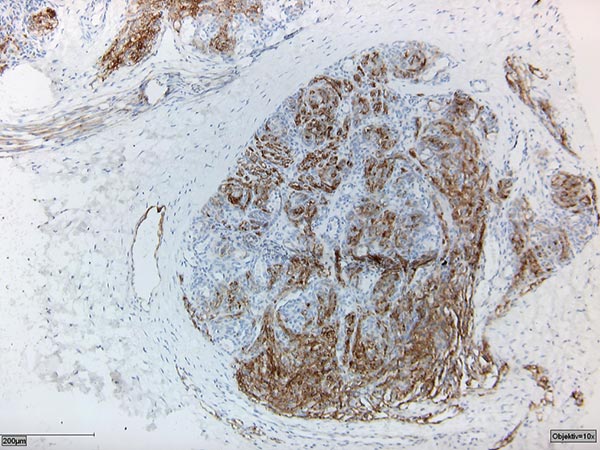

Histopathologic specimen in podoplanin stain (D2-40).

The D2-40 positivity for lymphatic endothelium together with the appearance of a vascular tumor confirmed the diagnosis of kaposiform hemangioendothelioma.